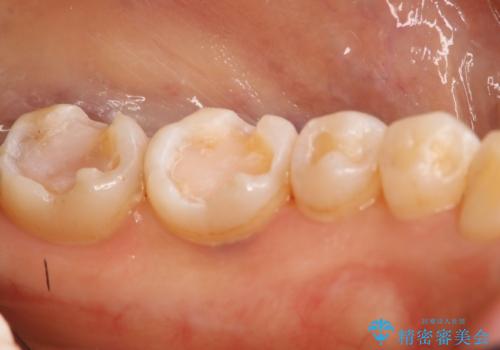

- 左下奥歯のメタルインレーを白くしたいと希望された患者様です。

形態、切削量などを考慮し、セラミックインレーにて治療を行いました。

メタルインレー、う蝕除去後にCRにて裏層した上で、形成・印象を行いました。